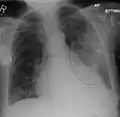

AP CXR showing left lower lobe pneumonia associated with a small left sided pleural effusion -

AP CXR showing right lower lobe pneumonia -

AP CXR showing pneumonia of the lingula of the left lung -

Right upper lobe pneumonia as marked by the circle. -

Left upper lobe pneumonia with a small pleural effusion.

Right lower lobe pneumonia as seen on a lateral CXR

The discovery of x-rays made it possible to determine the anatomic type of pneumonia without direct examination of the lungs at autopsy and led to the development of a radiological classification. Early investigators distinguished between typical lobar pneumonia and atypical (e.g. Chlamydophila) or viral pneumonia using the location, distribution, and appearance of the opacities they saw on chest x-rays. Certain x-ray findings can be used to help predict the course of illness, although it is not possible to clearly determine the microbiologic cause of a pneumonia with x-rays alone.